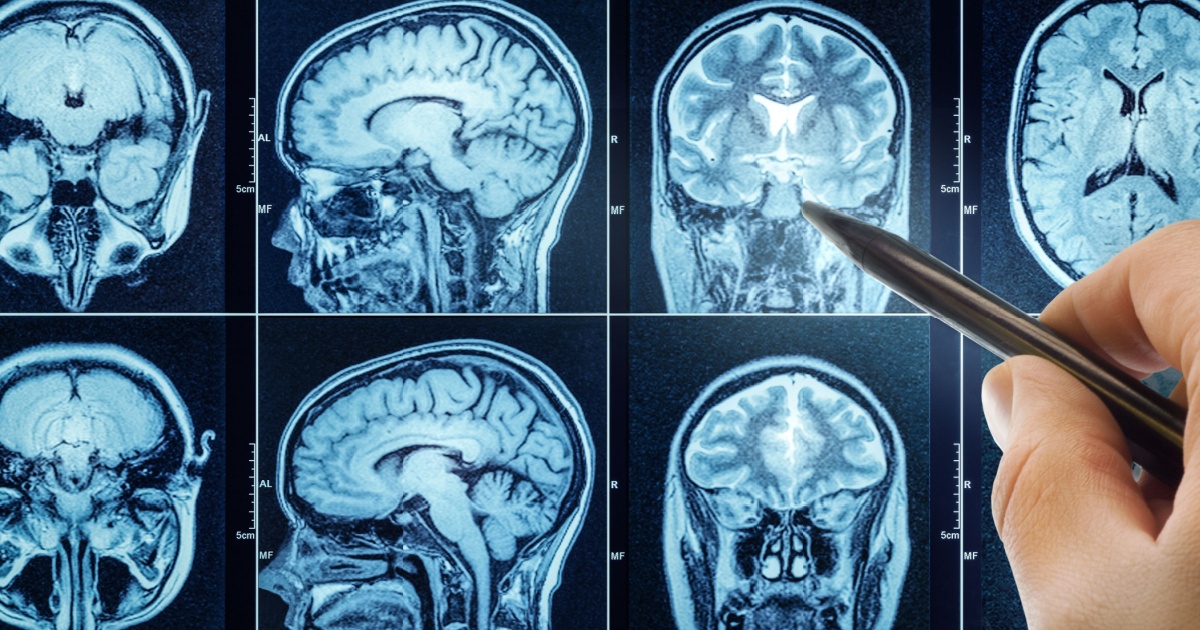

If you have ever watched a medical drama like Grey’s Anatomy, you know that computed tomography (CT) scans are very common. They are used to find tumors, locate blood clots, diagnose many types of cancers, get detailed images of broken bones, and much more.

CT scans work using X-rays just like traditional X-ray machines, except that the X-ray itself is spun around the patient to take much more detailed images. This means greater exposure to the ionized radiation, which can cause cancer.